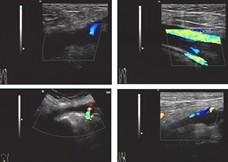

2009年1月6日(即术后27天),患者因“左全髋关节置换术后左小腿肿胀一周,进行性加重”入院。入院体检:左膝关节以下重度肿胀,皮肤发亮,皮温稍 高,轻压痛,左足部感觉、运动、血运可。1月7日行左下肢动静脉彩超示:左侧胫后静脉近心端内异常实质性回声,考虑深静脉血栓形成,双侧胫前静脉显示不 清。凝血五项示:APTT:22.7 (正常24.5—36.0),D-二聚体1667 μg/L (正常0—324μg/L)。诊断为左小腿深静脉血栓。予以速碧林,低分子右旋糖苷等药物抗凝,对症支持,患者左小腿肿胀部分缓解。09年1月14日复查 左下肢动静脉彩超示左侧股静脉,腘静脉及胫后静脉近心端内异常实质性回声,考虑深静脉血栓形成。同日复查凝血五项示:APTT:24.3(正常24.5— 36.0),D-二聚体546 μg/L (正常0—324μg/L)。考虑患者左下肢血管栓塞范围较广,请血管外科会诊后转入血管外科继续进一步治疗。转入血管外科后,予病人速碧林抗凝,尿激酶 溶栓,同时对症支持治疗。1月16日复查左下肢血管彩超示:左侧腘静脉内异常实质性回声,考虑深静脉血栓形成不完全阻塞。1月22日复查凝血五项 示:APTT:24.1(正常24.5—36.0),D-二聚体204 μg/L (正常0—324μg/L)。患者左下肢肿胀明显减轻,胫前仍有轻微水肿,生命征稳定,无诉其他不适。考虑患者病情明显好转,予以出院,嘱其院外继续抗凝 治疗,定期复查凝血功能,不适随诊。

彩色多普勒是检查下肢深静脉血栓形成的无创方法,可反复检查,诊断率可达 90%。血栓形成时主要表现为深静脉管腔扩张、管腔内充满大量低弱回声物,无血流通过征象,治疗好转者表现为深静脉管腔变窄,管腔内低弱回声物减少,有血 流通过征象。静脉造影敏感性和特异性均较高,但其为有创检查。阳性结果主要为静脉内出现恒定的缺损、正常充盈的静脉突然中断、静脉主干不显影等。一般主张 对下肢手术后出现小腿疼痛患者立即行影像学检查,首选彩色多普勒检查。而彩色多普勒在本例患者的诊断,判断治疗效果方面也呈现重要作用。